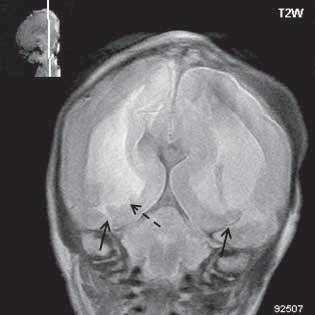

Obr. I.1.8e Dandy-Walkerovo spektrum (hypoplazie vermis, IV komora je rozšířená a široce zeje) (snímky zapůjčeny z archivu as MUDr J Lisého, CSc )

Obr. I.1.8f Dandy-Walkerovo spektrum (hypoplazie vermis, IV komora je rozšířená a široce zeje) (snímky zapůjčeny z archivu as MUDr J Lisého, CSc ); stejný pacient jako na obr I 1 8e

Obr. I.1.8g Dandy-Walkerovo spektrum (hypoplazie vermis, IV komora je rozšířená a široce zeje), (snímky zapůjčeny z archivu as MUDr J Lisého, CSc ); stejný pacient jako na obr I 1 8e, f

D-W malformace je charakterizována hypoplazií vermis mozečku, rozšířením IV. mozkové komory, která se často cysticky vyklenuje dorzálně a může imitovat arachnoidální cystu, rozšířením zadní jámy lební a vysokým úponem tentoria s confluens sinum nad lambdovým švem. Okcipitální kost může být vlivem tlakových změn remodelována, existují i případy s porušením její kontinuity a encefalokélou. Hydrocefalus pozorujeme v 80 %, častá je přítomnost dysgeneze corpus callosum, schizencefalie.

D-W variant byl vyčleněn pro případy, kdy všechny základní příznaky nemusí být plně vyjádřeny nebo může některý zcela chybět. Bývá přítomna hypoplazie mozečku, což je dominantní příznak, IV. komora je obvykle rozšířena, někdy pozorujeme, že tvarem připomíná na axiální řezu „klíčovou dírku“, zadní jáma lební naopak rozšířena nebývá.

Retrocerebelární vak (Blake’s pouch cysta) vzniká embryonálně vyklenutím části stropu IV. komory (velum

mediale superius) do cisterny magna (vak je vyplněn likvorem, chybí foramen Magendii). Je charakterizován rozšířenou a široce otevřenou IV. komorou, která komprimuje bazální cisterny, hypoplazie vermis mozečku naopak není přítomna. Široce komunikující IV. komora (někdy obsahuje choroidální plexus), přičemž komunikace mezi komorovým systémem a subarachnoidálními prostory je pouze přes laterální foramina Luschkae.